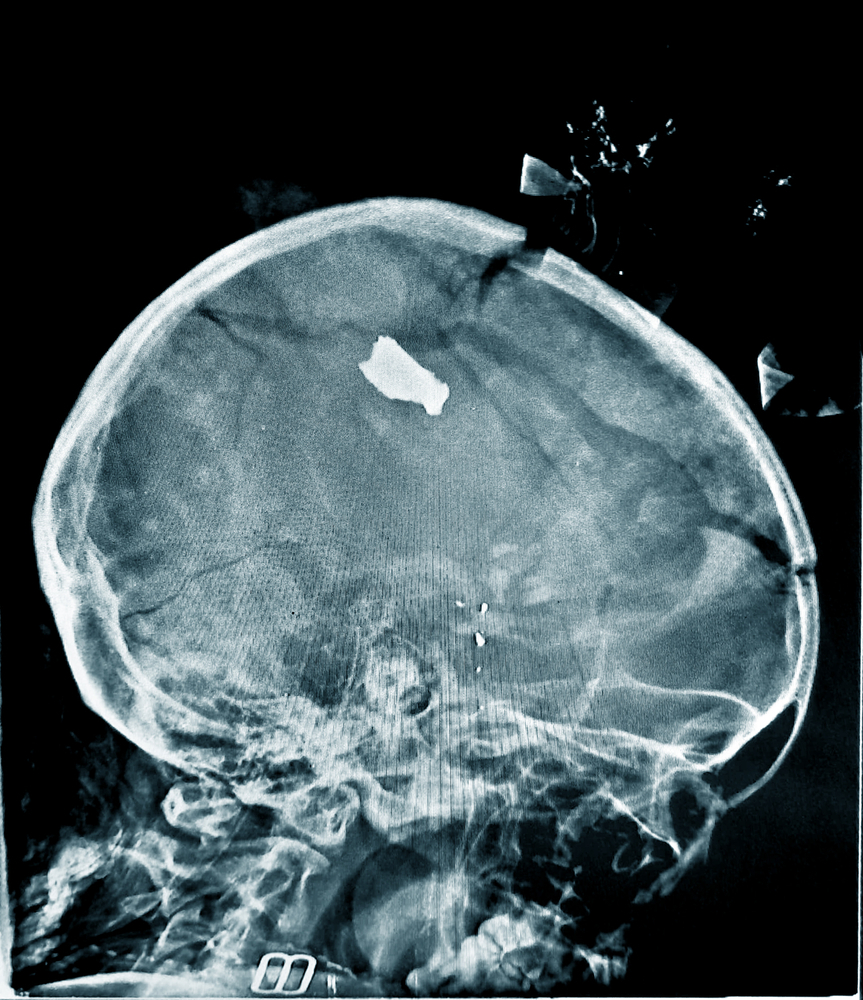

Nos últimos 12 meses, as equipes de Médicos Sem Fronteiras (MSF) testemunharam a continuação e a escalada de conflitos, como em Gaza e no Sudão, onde guerras ininterruptas chegaram ao seu segundo ano.

Esta seleção de fotos, capturadas entre janeiro e dezembro de 2024, apresenta os altos e baixos do trabalho médico-humanitário que fornecemos em mais de 70 países.

O atendimento médico proporciona alívio nas circunstâncias mais difíceis. Continuamos inspirados pelo compromisso de nossa equipe em oferecer assistência às pessoas, mesmo com obstáculos crescentes.